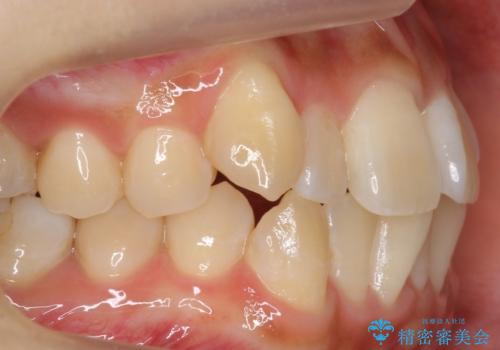

八重歯 インビザラインで抜歯矯正 ただし1本のみの抜歯で済みます

- 八重歯を治したいと来院。

古典的な治し方ですと上下左右4本抜歯してワイヤー矯正です。

今回は口元も出ていないうえに、右上のみの八重歯のため奥歯を後ろに下げて治療しました。

ただし、下の前歯は入りきらない為1本のみ抜歯しています。

右上の犬歯をおろしてくるのに、顎間ゴムを使用しています。